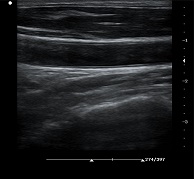

支持凸陣、線(xiàn)陣、腔內(nèi)、相控陣、小微凸等探頭

? ?● 血管內(nèi)中膜自動(dòng)測(cè)量

? ? ? ?操作簡(jiǎn)單,提高工作效率